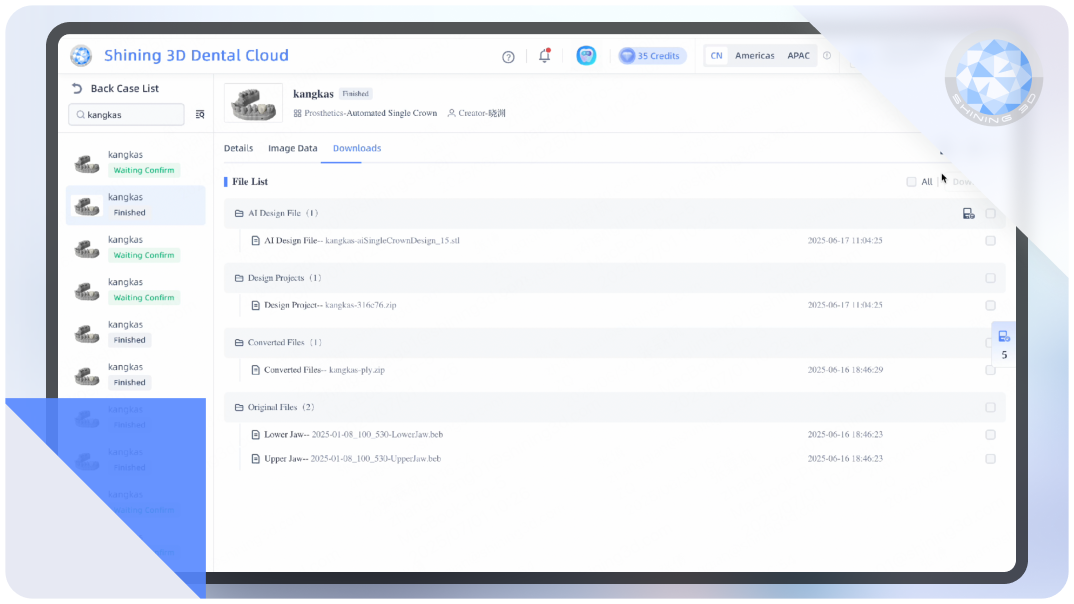

AI Crown

Intelligently generates dental crowns, auto-filling undercuts with meticulous precision.